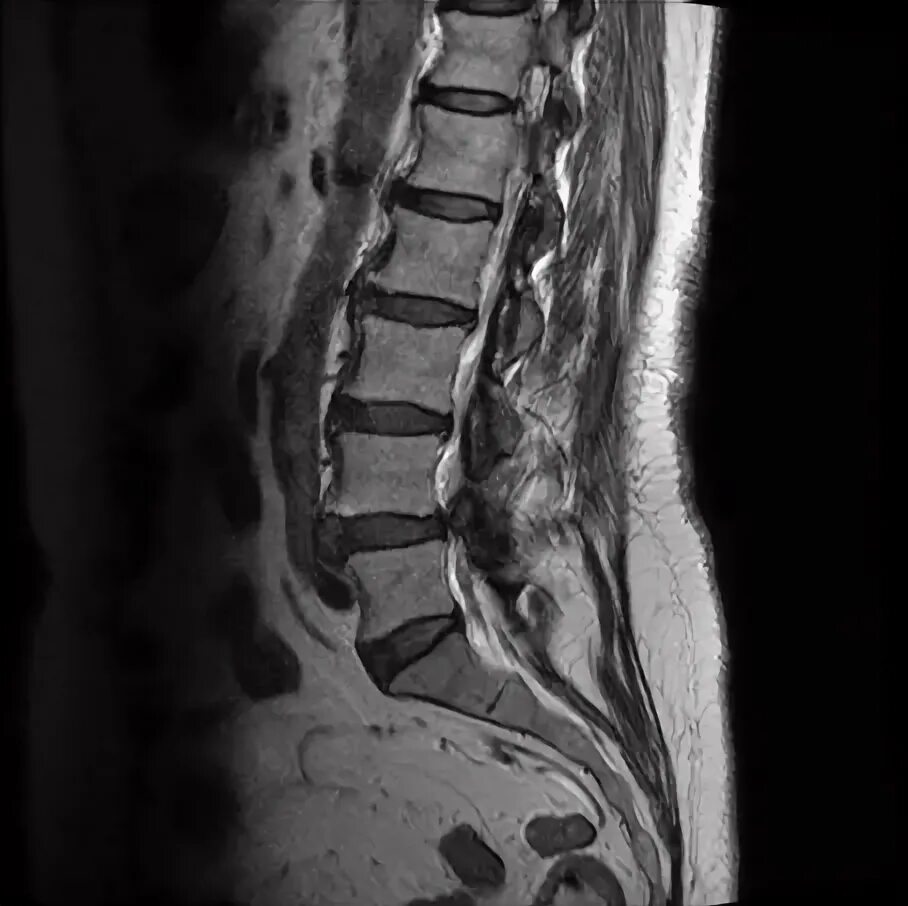

Деформация дурального мешка поясничного